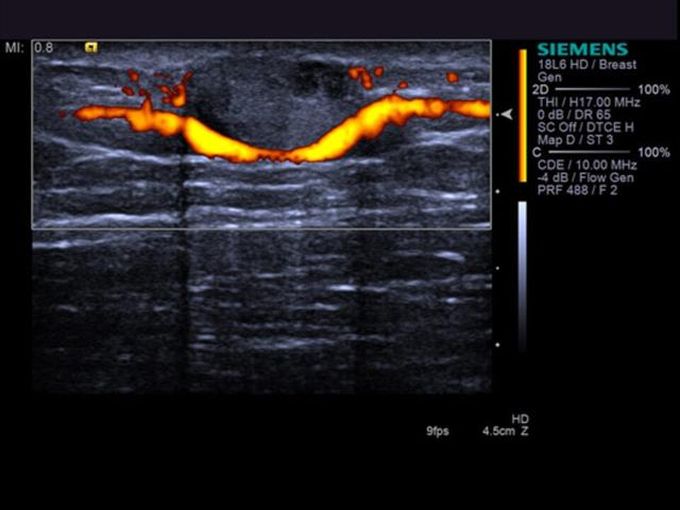

Кроме новой техники, можно заказать восстановленные медицинские системы: ультразвуковые сканеры, томографы, флюороскопы, ангиографы и хирургические установки С-дуга.